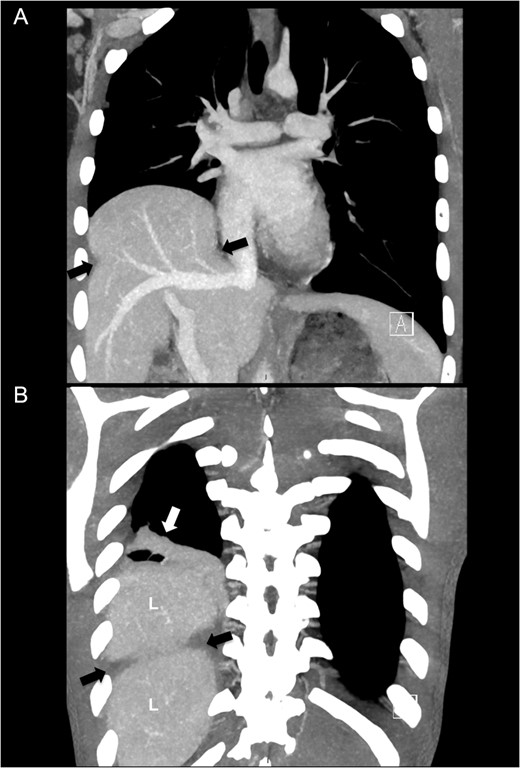

On admission after transfer to our hospital he had stable vital signs, with none or little complaints or symptoms. The transferred radiological images from the primary hospital were reviewed and gave immediately suspicion of additional pathology in the right hemithorax, based on a prominent right-sided high-stand of the diaphragm (Fig. 1). A CT scan was made showing a grade II liver laceration and a herniated liver through a large right-sided defect of the right diaphragm (Fig. 2A and B).

Computed tomography of right-sided diaphragm rupture and herniated liver. (A) CT performed after transfer showing ruptured diaphragm (black arrows) with herniated liver into the right thoracic cavity. (B) A more posterior view with pulmonary atelectasis (white arrow). L denotes liver.